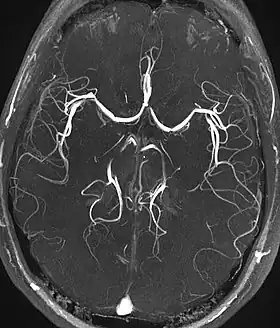

| Magnetic resonance angiography (MRA) and venography | Time-of-flight | TOF | Blood entering the imaged area is not yet magnetically saturated, giving it a much higher signal when using short echo time and flow compensation. | Detection of aneurysm, stenosis, or dissection[40] | ![]() |

| Phase-contrast magnetic resonance imaging | PC-MRA | Two gradients with equal magnitude, but opposite direction, are used to encode a phase shift, which is proportional to the velocity of spins.[41] | Detection of aneurysm, stenosis, or dissection (pictured).[40] | ![]() (VIPR) |